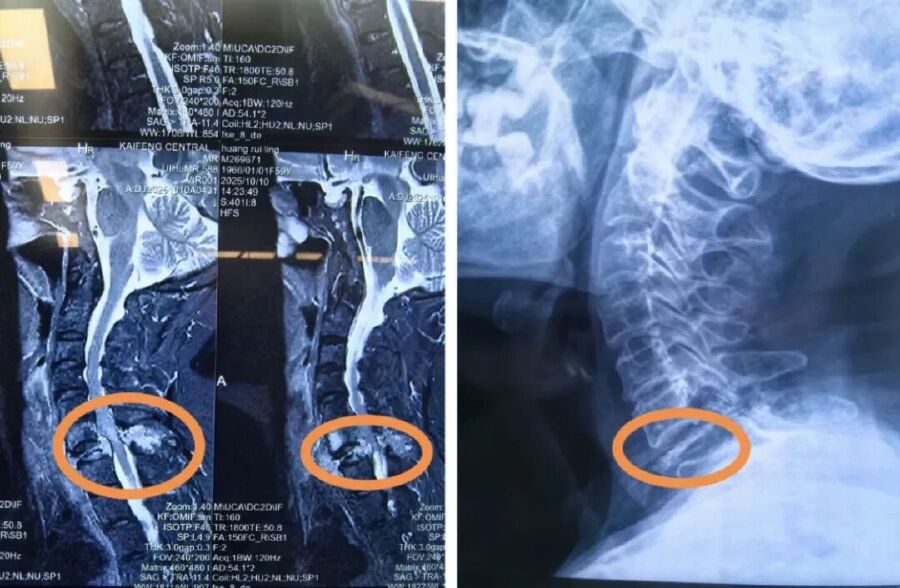

術前的核磁示:頸7椎體及附件區可見腫瘤侵犯信號

頸椎DR示:第7頸椎椎體明顯破壞并壓縮